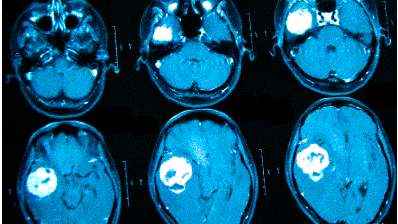

Онкологи считают, что при нарастающих головных болях с прочими необъяснимыми симптомами (обмороками, ухудшением памяти, выпадением полей зрения, давлением на глазные яблоки и др.) в первую очередь следует исключить опухолевую патологию

Частые головные боли вызывают разные причины. Иногда так проявляется серьезное заболевание. В 90% случаев после определения генеза возможно адекватное лечение, которое улучшит качество жизни. Состояния, для которых типична цефалгия::

• опухоли;

Если причина не установлена, обосновано прохождение МРТ головы при головных болях. Не стоит подозревать у себя смертельную патологию. Например, если болит затылок, возможной причиной является переутомление, а нормализация режима труда и отдыха поможет справиться с проблемой. При повышенном давлении часто присутствует головокружение, покраснение кожных покровов, шум в ушах. Боль в лобной части головы вторична и проходит после приема гипотензивного лекарства. Но гипертония может быть связана с патологией сосудов или опухолевой компрессией, поэтому прохождение МРТ при сильных головных болях — важный аспект в дифференциальной диагностике.